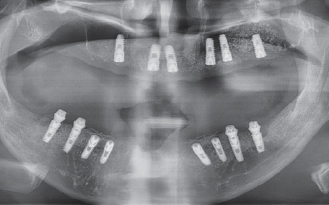

수술 전 파노라마

수술 후 파노라마